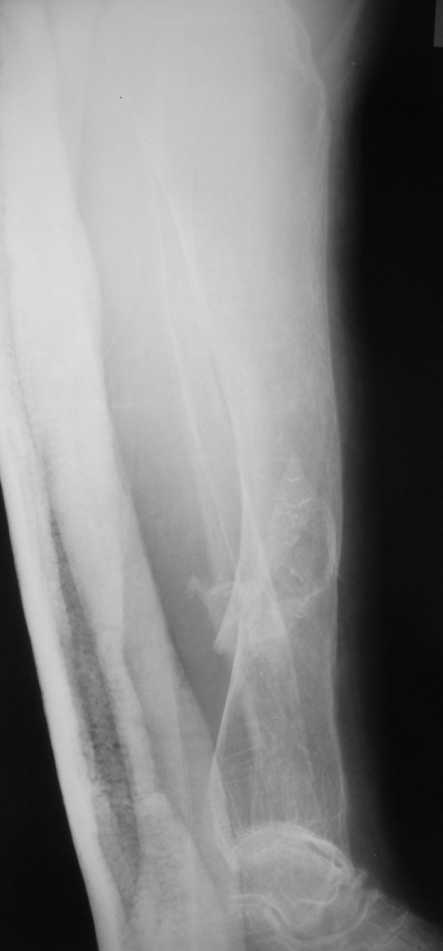

Уважаемые коллеги! Здравствуйте! Прошу у Вас совета вот по какому случаю.В нашу клинику поступила женщина 71 год. Травма в результате ДТП. (Пациентка передвигалась на инвалидной каляске и была сбита автомобилем). Диагноз: Множественная травма. Перелом нижней трети правого бедра. Перелом средней трети правой б/берцовой, малоберцовой кости, нижней трети левой большоберцовой, м/берцовой кости.Травматический шок. Со стороны внутренних органов и систем без патологии. Больная госпитализирована в реанимационное отделение, где было наложено двойное скелетное вытяжение за правую н/конечность. Левая н/конечность иммобилизована гипсовой лонгетой. Из анамнеза: больная является инвалидом 1 группы по опорно-двигательному аппарату. В детстве перенесла рахит. Осложнением которого "О" образная деформация нижних конечностей. Ограничено отведение нижних конечностей, деформирующий артроз тазобедренных и коленных суставов. В 1990 году перелом правого бедра остеосинтез пластиной. После операции больная передвигалась только на костылях или в инвалидной коляске.

Но даже при малоинвазивной методике лечения применимой для даной больной существуют следующие проблемы: выраженный остеопороз, тонкий кортикал, очень широкий канал.

Проблема в том, что в сагитальной плоскости угол голеней =30 градусам. Ширина канала 30.

Если при введении стержня будет видно, что из-за искривления дело идет к перфорации стенки, надо будет сделать чрескожную остеотомию на уровне кончика стержня.

ДС> Будет ли остеосинтез стержнем стабильный?

Во-1-х, интрамедулярный остеосинтез относится к методам, дающим относительную, не абсолютную стабильность. Во-2-х, стабильность неплохо обеспечивается запирающими винтами. В-3-х, несоответствие кривизны стержня и канала приводит к повышению стабильности, в-4-х, канал можно искусственно сузить введением отклоняющих (трансмедуллярных, Poller) винтов.

ДС> И возможны ли другие варианты остеосинтеза?

Конечно, возможны - любые существующие. Но оптимальным из возможных здесь однозначно является закрытый интрамедуллярный остеосинтез.